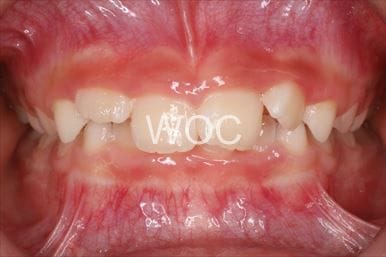

治療前3

治療後3